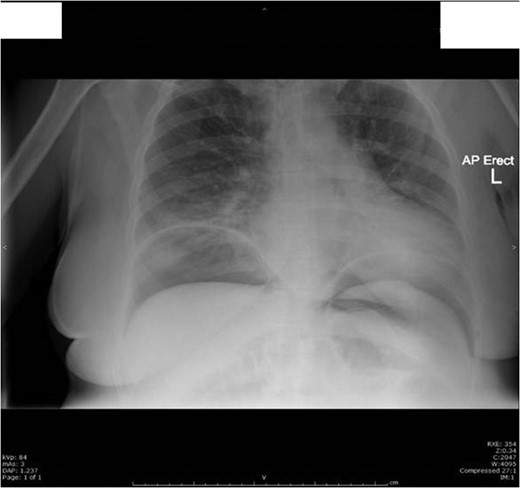

The next day she had fever with rigors, night sweats, ongoing abdominal pain and distension. Her bowel sounds were reduced and she had stopped passing flatus. She was treated for sepsis with likely respiratory source and commenced on intravenous antibiotics. On Day 4 post op she woke up with severe right shoulder tip and right upper quadrant pain radiating to her back. Her chest X-ray showed evidence of pneumoperitoneum (Fig. 3).

Day 4 post op chest X-ray showed a large volume of free gas under both hemi-diaphragms with multiple abnormally dilated loops of large and small bowel-features consistent with perforation of a hollow viscus.